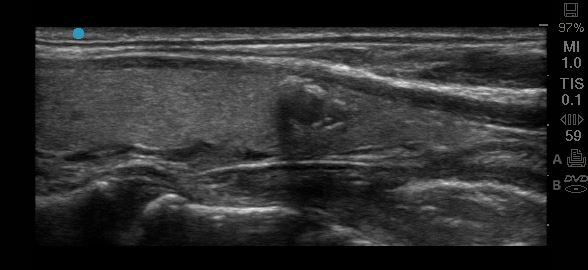

Artefactos acústicos leves - Imagen